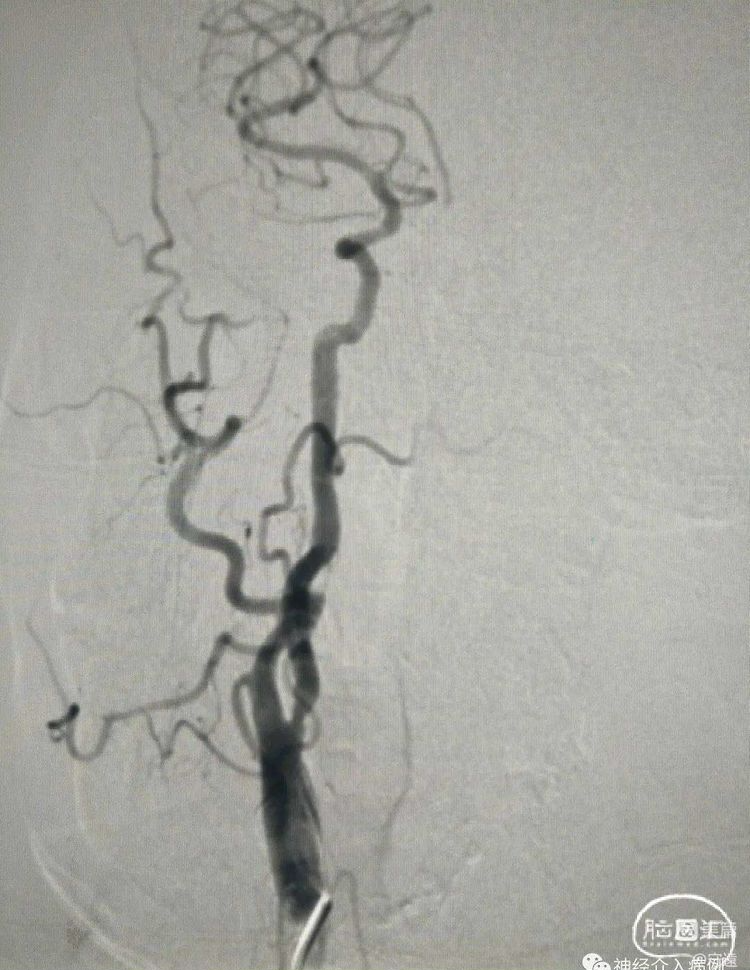

无症状性左侧颈内动脉起始段重度狭窄支架置入术(预扩张+锥形自膨式支架置入)

DSA:左侧颈内动脉起始段重度狭窄性钙化斑块,无前后交通动脉开放。

保护伞下,(4×30mm)球囊扩张。

置入锥形自膨式支架(8-6×40mm)。